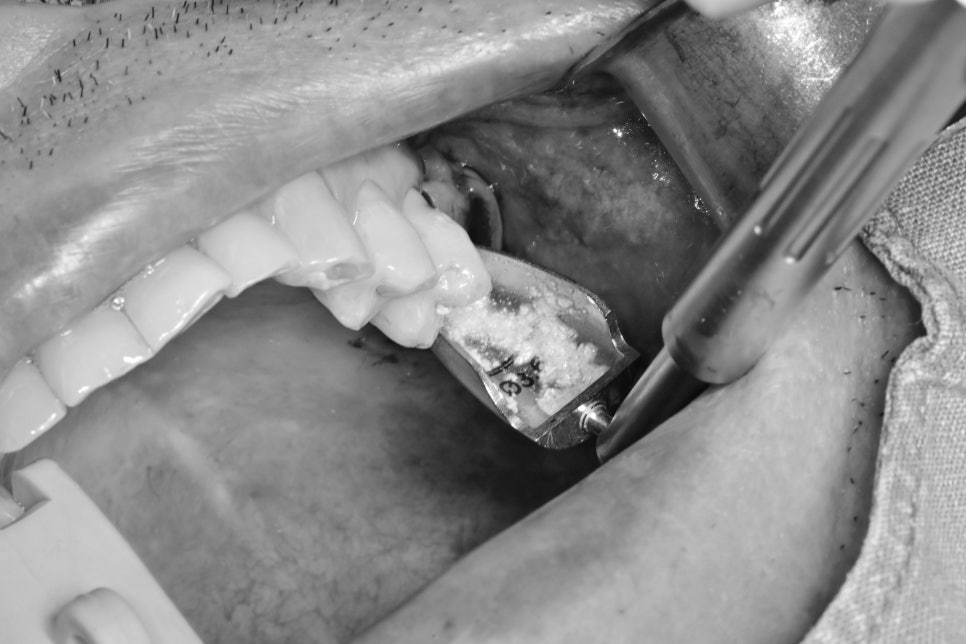

상악동 거상술의 여러 가지 방법

상악동을 살짝 거상하기 위해서는

추가적인 기구 조작이 필요한데 섬세한 작업을 요합니다.

방법에는 여러 가지 방법이 존재합니다.

물리적으로 뼈를 밀어올리는 방법

수압거상이라고 하는 물을 이용해 올리는 방법

기타 등등의 방법이 있지만

제가 말씀드릴 방법은 요즘 제가 사용하고 있는 방법은

뼈이식과 함께 상악동 막을 거상하는 방법입니다.

모든 방법이 검증이 완료된 술식이기 때문에

뭐가 특별하게 좋다고 말할 수 없지만

저는 이 방법이 수술 진행시 거상량이나 진행 상황을

직관적으로 판단할 수 있어서 추가적인 재료를 이용해 사용하고 있습니다.

상악동 거상을 하기 위해 뼈이식재를 담은 시린지입니다.

바나나처럼 휘어있어서

바나나테크닉이라고 하는데요.

상악동 입구까지는 전용 키트를 사용하여 길을 조심스럽게 만들어준 후

막을 조심스럽게 올려줍니다.

중간중간 엑스레이를 찍어가며 거상된 것을 확인하면

임플란트를 식립하기 전에

부족한 공간에 사진과 같이 뼈이식재를 추가로 더 넣어주고 수술을 마쳤습니다.